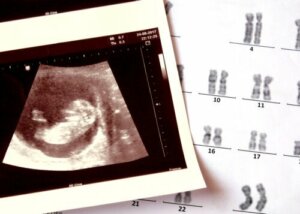

Gli esperti del Centro per il controllo e la diagnosi delle malattie (CDC) affermano che le cause dell’anencefalia non sono ancora conosciute con esattezza, ma è noto che si verificano a causa dell’interazione tra fattori genetici e ambientali.

Al suo aspetto potrebbero contribuire alterazioni cromosomiche (strutture che ospitano tutti i geni nelle cellule) e alcune mutazioni puntiformi. È stato inoltre studiato che l’esposizione ad alcune tossine ambientali potrebbe essere determinante, sebbene al momento i risultati delle indagini non siano conclusivi.